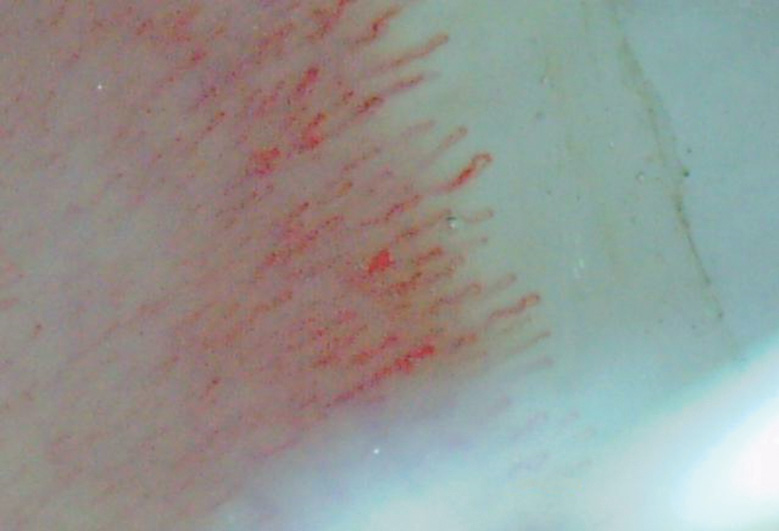

In the comparison groups, the capillaroscopic pattern was represented by single pathological changes in the capillaries that did not indicate pathognomonic sclerodermic patterns, except for the group with dermatomyositis/polymyositis where significant Raynaud’s syndrome was diagnosed in two patients (Figs. 6–9).

Fig. 7. Pathological changes of the capillary bed in the group of patients with osteoarthritis

Рис. 7. Патологические изменения капиллярного русла в группе пациентов с остеоартритом

In 20 patients with osteoarthritis, NFC showed dilatation and pathological tortuosity of the capillaries (n = 2 each) in all study fields. These abnormalities are clinically insignificant and may be caused by angiopathy in nodular osteoarthritis.